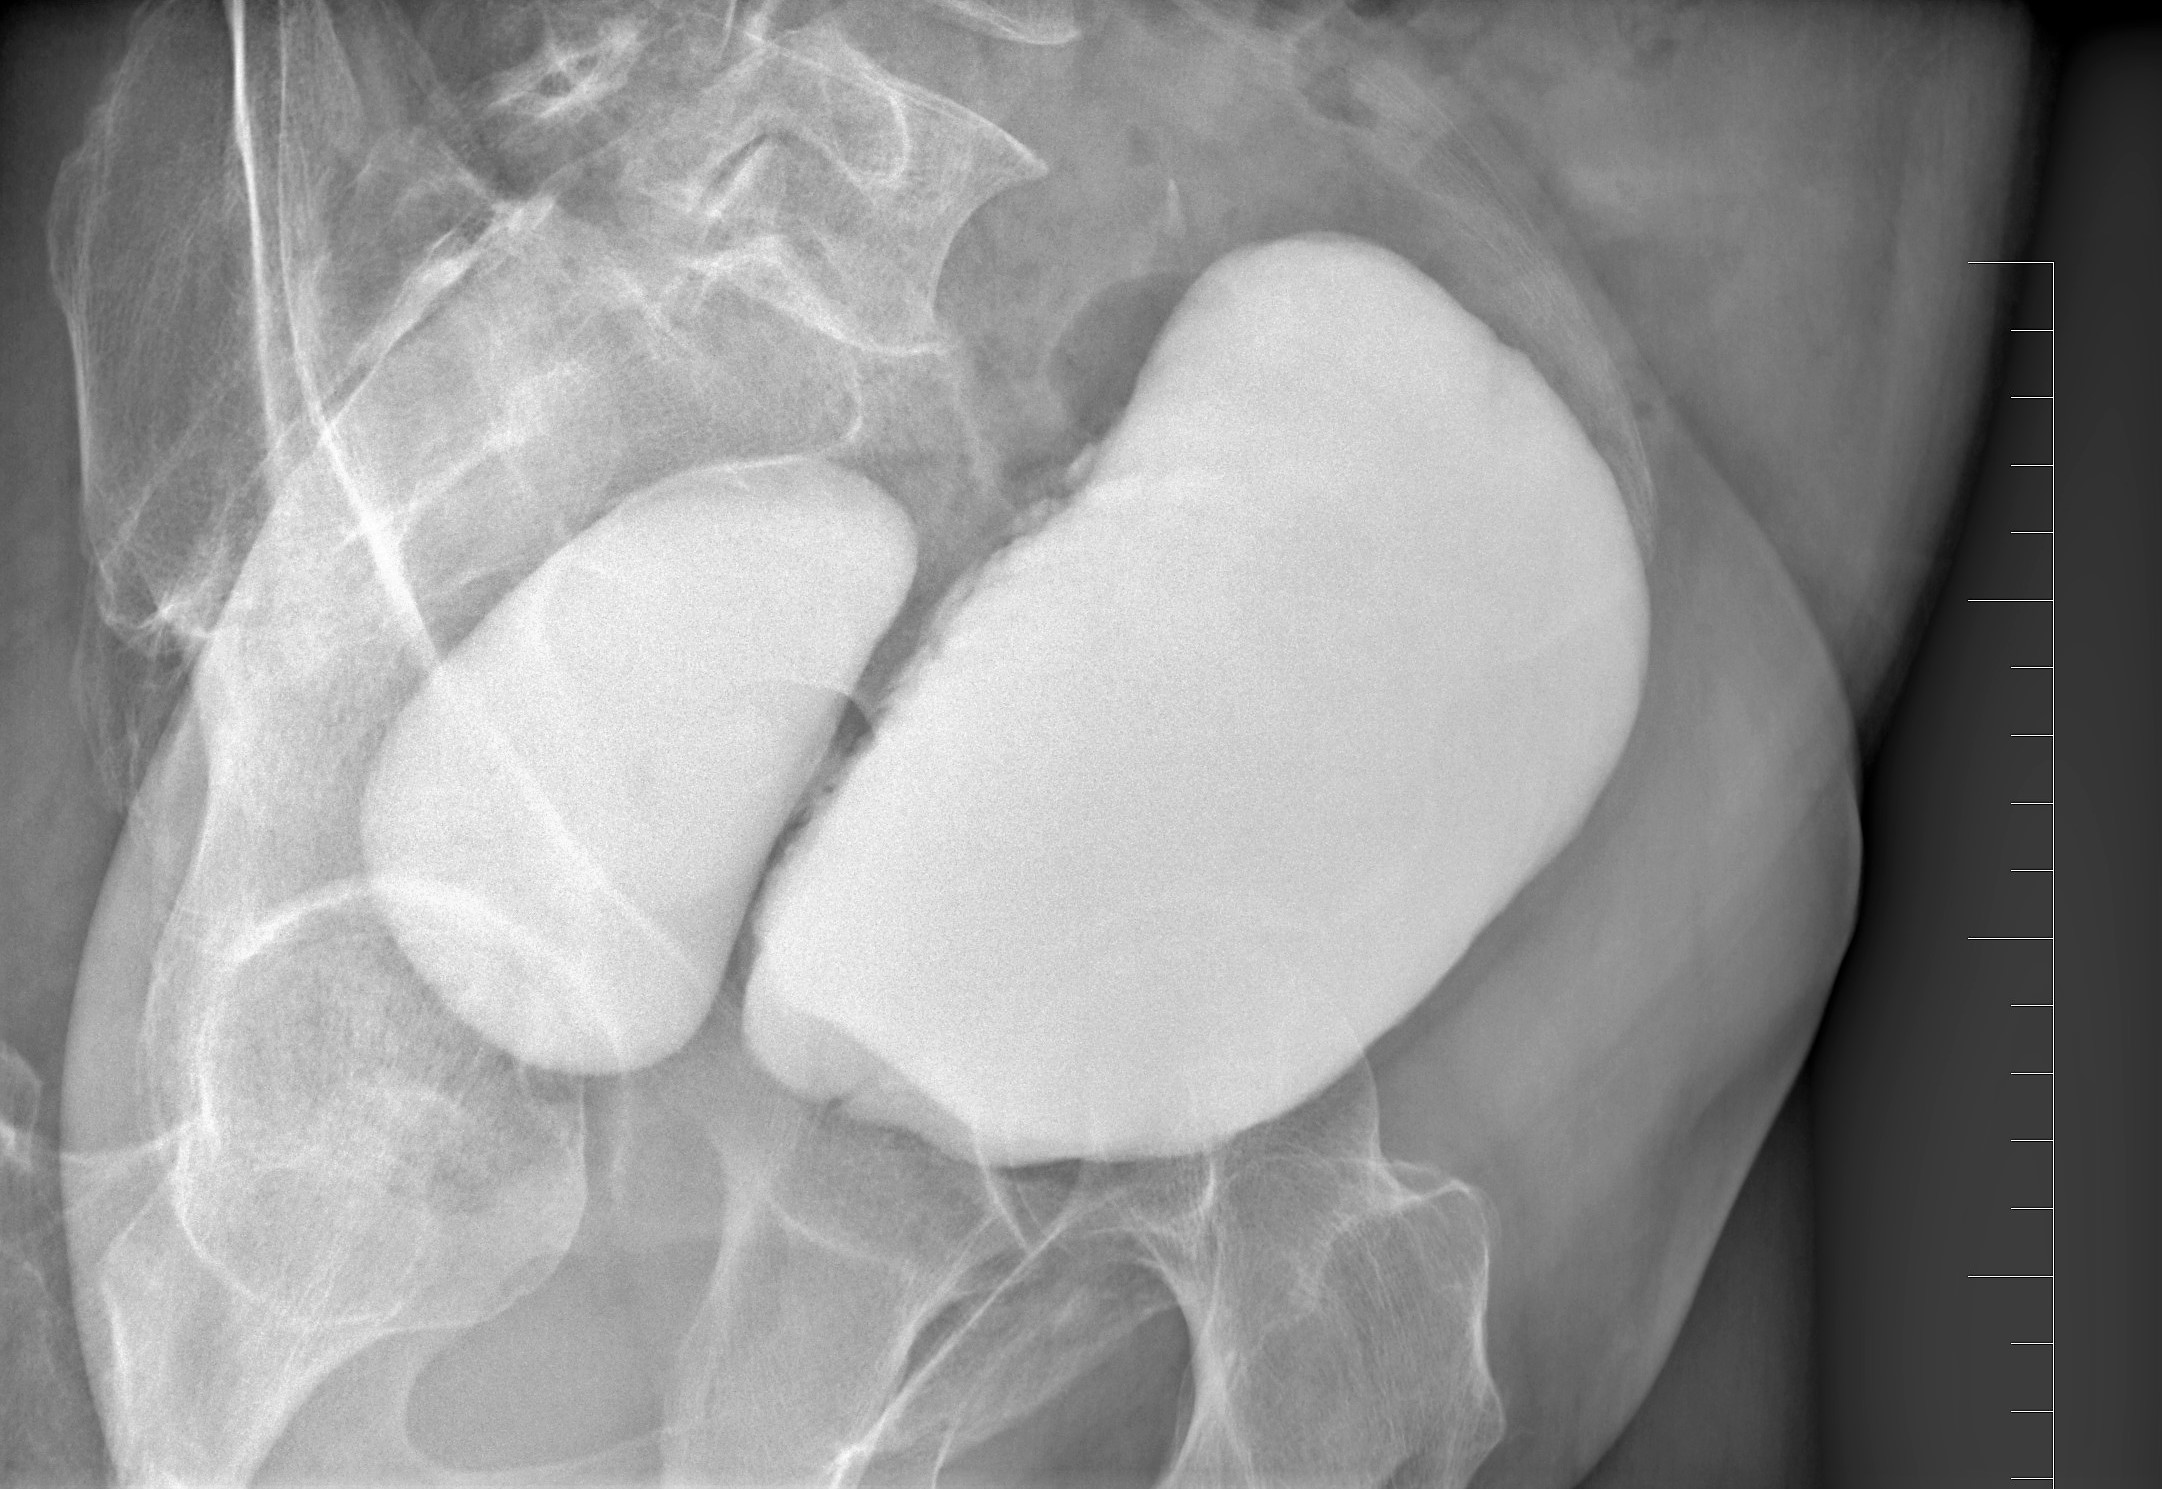

Divertiklem je v lékařské terminologii označena výchlipka, výduť dutého orgánu těla, jako je právě močový měchýř. Lze si ji představit tak, že normální tvar orgánu třeba vzhledu nafouknutého balonku narušuje menší vyboulenina, která je s močovým měchýřem spojená, a tudíž má společnou výplň – moč. Příčinou jejího vzniku je překážka v odtoku moči močovou trubicí, často jde o zvětšenou prostatu nebo třeba zúženinu močové trubice. Z tohoto důvodu se s těmito problémy potýkají mnohem častěji muži.